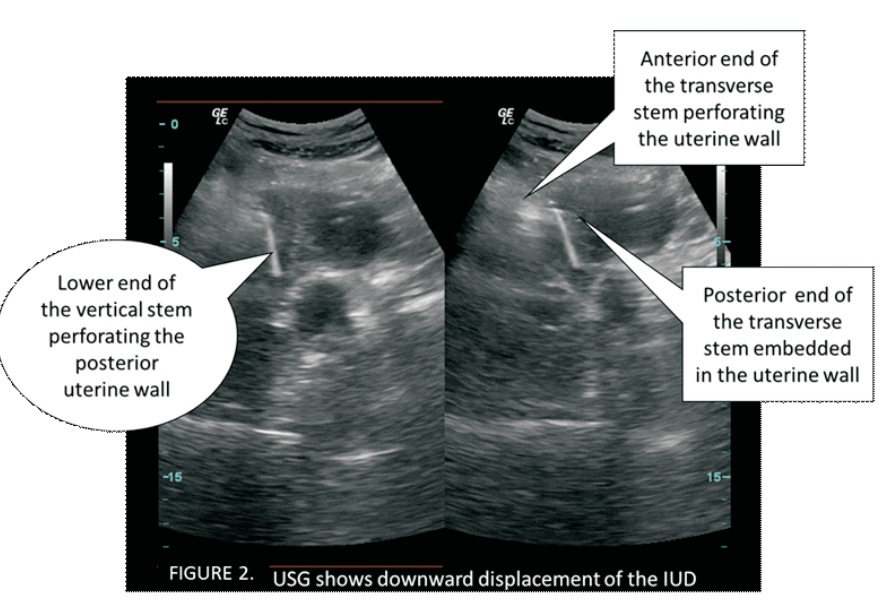

Secondary perforation with post placental intra uterine device: A case report

Sujnanendra Mishra (Author)

1635-1638

PDF